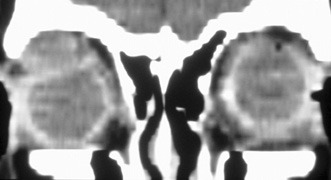

Magnetic resonance imaging is useful in selected cases, especially when evaluating the orbital cranial junction. Significant bony artifact and a lack of orbital fat in the orbital apex make CT scan resolution of the orbital apex structures poor. Because cortical bone has low signal on MRI, there is no bone artifact when viewing the orbital apex on MRI. The lack of intervening fat in the apex to provide contrast is overcome on MRI because contrast is provided by the individual nuclear characteristics of each tissue so that the orbital apex structures are visualized well. Consequently, conditions that affect the optic nerve and chiasm, such as optic nerve meningioma and glioma, generally are evaluated with MRI rather than CT scan (Fig. 2).

Fig. 2. A. Axial orbital CT scan of right optic nerve meningioma. Note lack of detail in orbital apex. B. Axial orbital MR image, same patient. Note increased detail in orbital apex owing to lack of bone artifact. C. MRI with gadolinium contrast. Note extension into brain not easily appreciated with CT scanning or MRI without contrast.